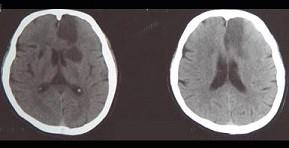

问题 患者,78岁,有高血压病史8年,突发一侧下肢无力,伴少语2天入院,行头颅CT出现如图所示脑梗死,该病灶最可能是下列哪条阻塞引起 ( )

选项 A、脉络膜前动脉 B、豆纹动脉 C、颈内动脉主干 D、大脑中动脉主干 E、大脑前动脉主干 一、单项选择题

答案 E